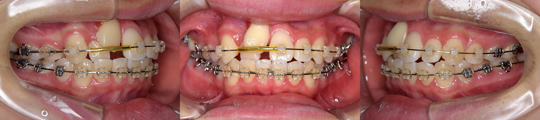

| 使用装置 | 上下顎マルチブラケット装置 |

| 治療期間、 治療回数、治療費 |

1年8か月、17回、645,015円 *動的治療終了まで |